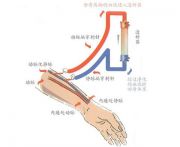

| 2021年7月26日 (一) 20:03 | 血液透析动静脉瘘.jpg (文件) |  |

27 KB | Uploaded with SimpleBatchUpload | 3 |